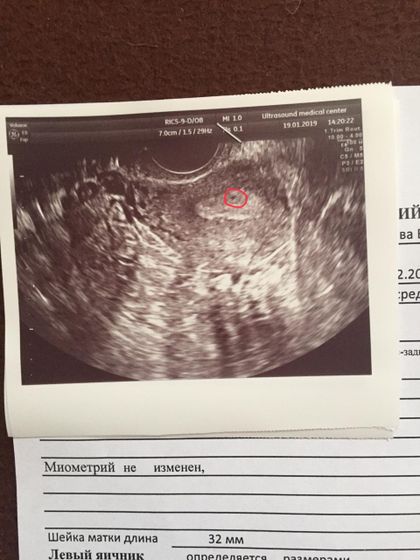

Тесты очень полосатые. Последние месячные 20.12.18. Была на узи, врач не увидел плодного Яйца, но я его четко вижу на снимке. Это же оно? Очень боюсь внематочной

Вы рано на УЗИ пошли. Дождитесь задержки в 2-3 недели.

У меня на таком сроке уже было в 10 больше. Либо очень поздняя овуляция, либо не оно.

Нет, слишком маленькое. Вот мое УЗИ в первую беременность. А так ещё рано не паникуйте, через неделю две переделайте

Сдайте на хгч, это будет надёжней. На плодное яйцо это не похоже.

Срок по месячным 4 недели, по зачатию около 2. Врач очень старый, мог не разглядеть мою бусинку

Кать, срок такой у тебя, что там рано ещё рассматривать, его будет отчётливо видно в нед 5-6. Сейчас это клетка, если она там есть. А вот результат хгч, покажет это — беременность есть или её нет.

Спасибо за добрые слова! Во вторник хочу сходить ещё раз, нужно исключить внематочную, у меня непроходимость труб. Дай бог чтобы это была моя бусинка?